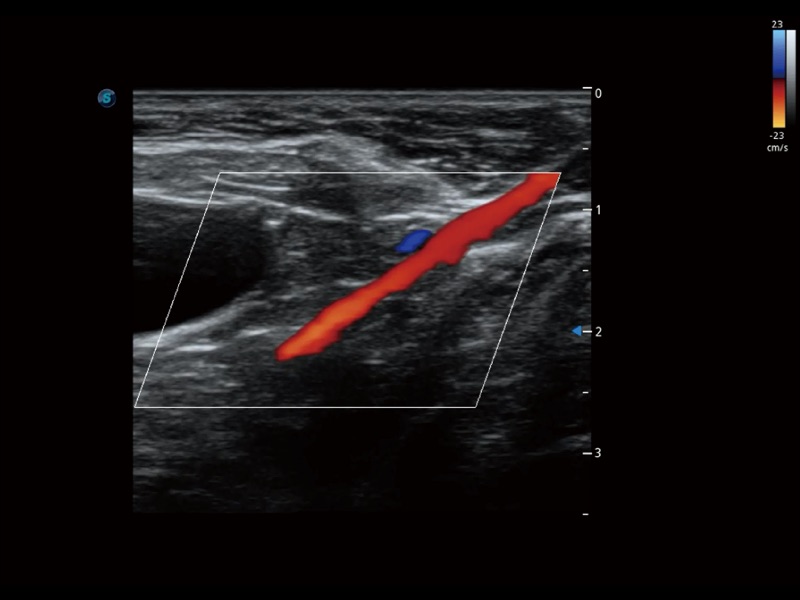

通過創(chuàng)新的 Matrix E自適應(yīng)濾波器和超長時間域算法,極大提升超低速微細血流的檢出能力,同時更精準地濾除軟組織和噪聲信號,為獸用醫(yī)生提供以往無法通過常規(guī)血流獲得的疾病診斷信息。

通過色彩血流和實時寬景相結(jié)合,可觀察到完整的靜脈或動脈的血流,方便醫(yī)生檢查。實時掃查過程中,如有任何操作失誤也可以很容易地進行回掃擦除,而不會中斷掃查。